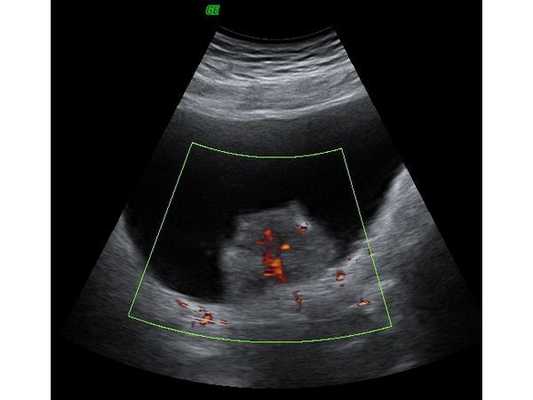

- по правой боковой стенке — светло-серое (изоэхогенное) неоднородное образование с нечёткими неровными контурами и единичными очагами кровотока размером 45×35 мм;

- содержимое мочевого пузыря — мелкодисперсная взвесь.